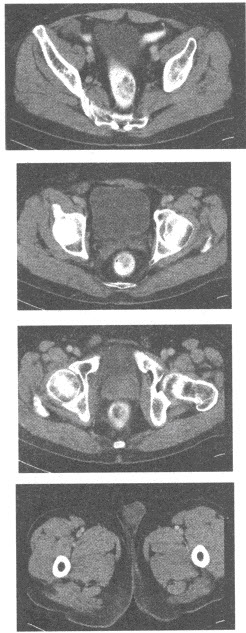

男,20岁,右侧阴囊空虚,触诊时阴囊内无睾丸,根据所提供的增强CT图像:

最可能的诊断是()

B、隐睾

B